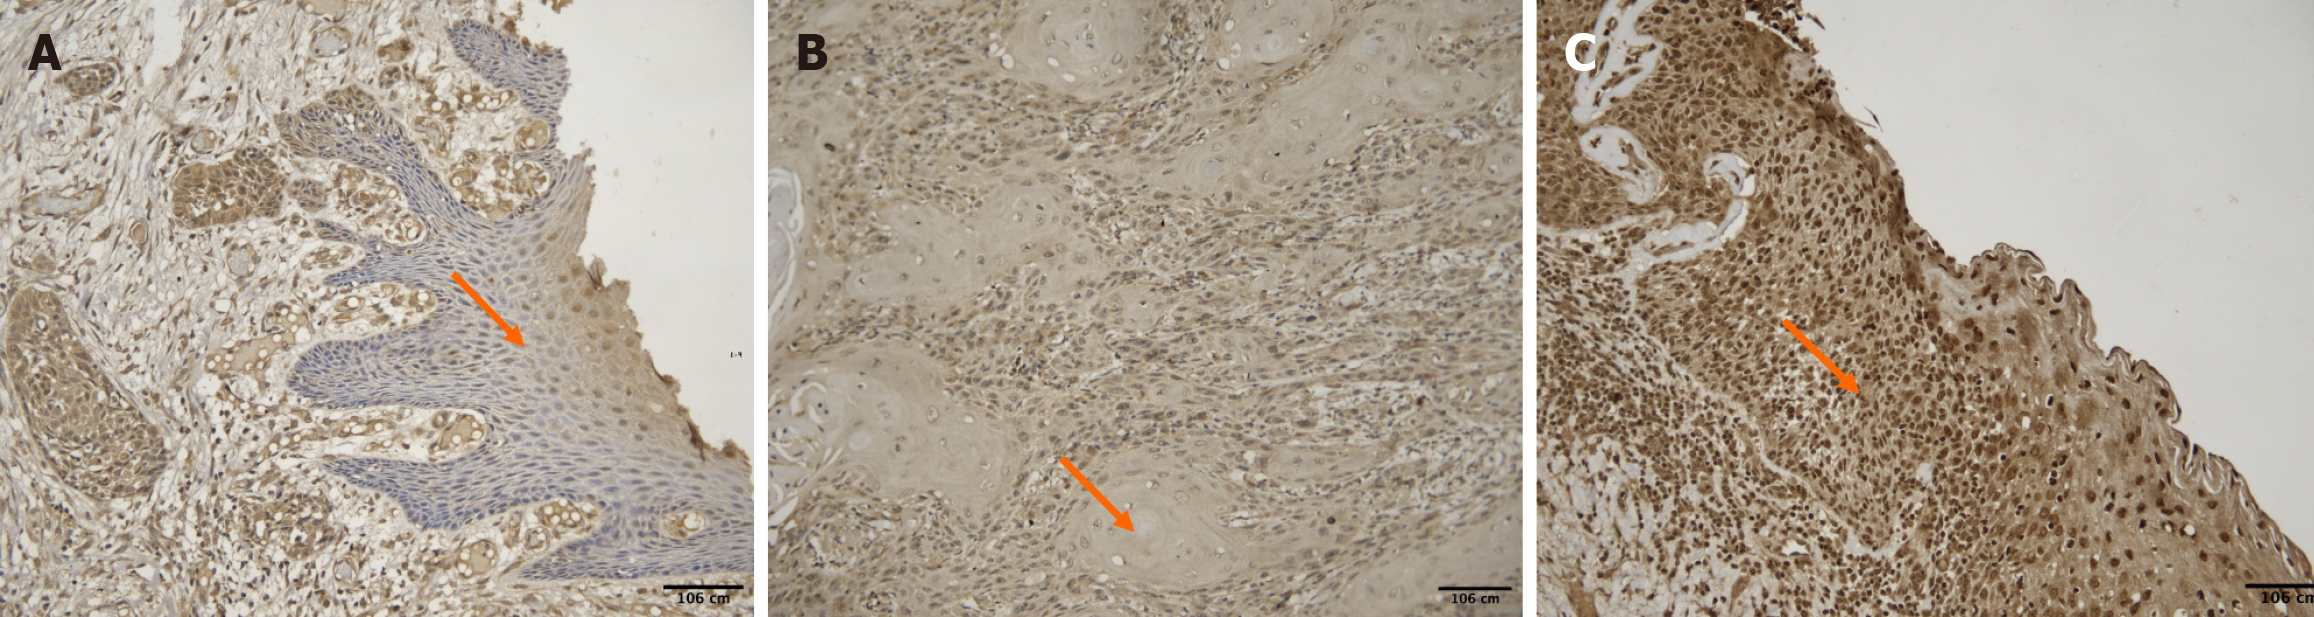

Figure 2 Images showing different intensities of palmitoyl-protein thioesterase 1 expression in oral squamous cell carcinoma cases (orange arrow denotes the tumor area).

A: Shows 3+ intensity [high intensity of palmitoyl-protein thioesterase 1 (PPT1) antibody in oral squamous cell carcinoma (OSCC) case]; B: Shows 2+ intensity (moderate intensity of PPT1 antibody in OSCC case); C: Shows 1 + intensity (mild intensity of PPT1 antibody in OSCC case); D: Shows no expression of PPT1 antibody in OSCC case.